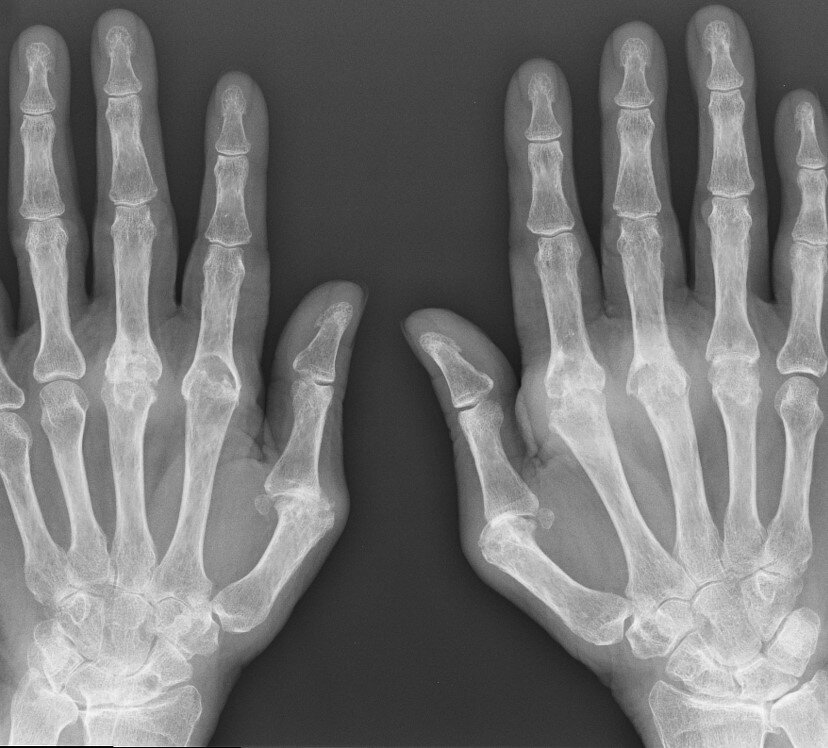

Два с половиной часа там, очередь, рентген - и в итоге диагноз - "ушиб средней фаланги безымянного пальца".